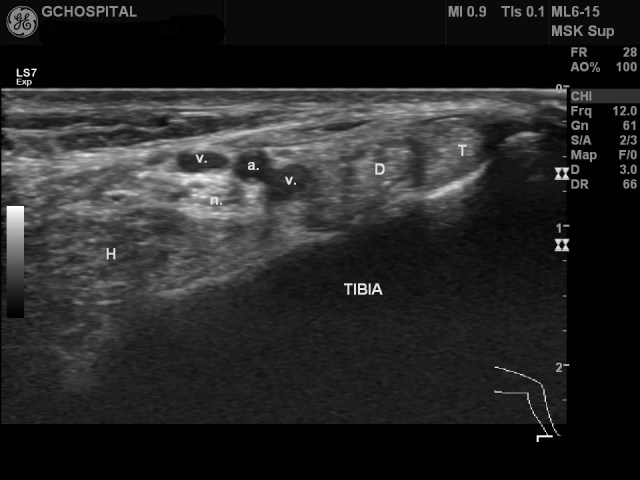

T : tibialis posterior tendon

D : flexor digitorum longus tendon

H : flexor hallucis longus

a. : posterior tibial artery

v. : posterior tibial veins

n. : posterior tibial nerv

내측 복사뼈보다 위쪽에서 얻은 발목 내측(posteromedial compartment)의 초음파영상입니다. flexor hallucis longus muscle과 tenon의 일부가 함께 보입니다. 통상 교과서를 보면, posterior tibial artery보다 posterior tibial nerve가 더 뒤쪽에 위치하는것처럼 기술되 있는 경우가 많은데, 실제로 보면 위의 영상처럼 뒷쪽이라기 보다는 더 깊은 곳에 위치해있는 경우가 더 흔한것 같습니다.

여기서 tibialis posterior nerve주변에 신경과 혈관을 압박하고 있는 구조물이 있는지를 확인하는 것이 발목쪽의 구획증후군(compartment syndrome)을 진단하는데 매우 중요합니다. 언급하고 있는 구조물들을 둘러싸고 있는 얇은 막이 flexor retinaculum입니다.